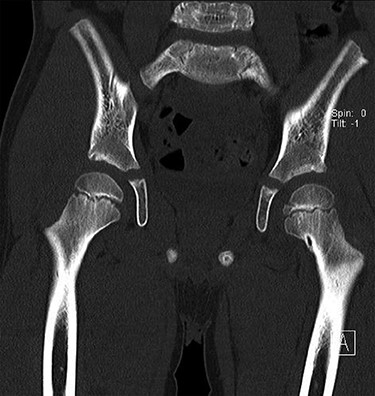

CT hips reported a well-defined lesion seen bilaterally in the neck of femur anterior infero-medial aspect, more prominent on the left side measuring 7 x 3 mm on left side both in coronal (Fig. 3) and axial (Fig. 4) views. On the right side, other lesion measuring 2 x 1 mm (Fig. 5) seen in coronal view. These two lesions are well defined with a sclerotic border with a small cortical defect. The lesion shows fat density. The symmetrical appearance of the lesion combined with the fat density and location suggest the diagnosis of synovial herniation pit. MRI Pelvis revealed minimal left hip joint effusion with loculated fluid seen along the trochanteric bursa with the largest measuring 0.9 x 1.5 cm (Fig. 6, 7).

Showed axial cut of CT hips demonstrating the synovial pit on left and right side.